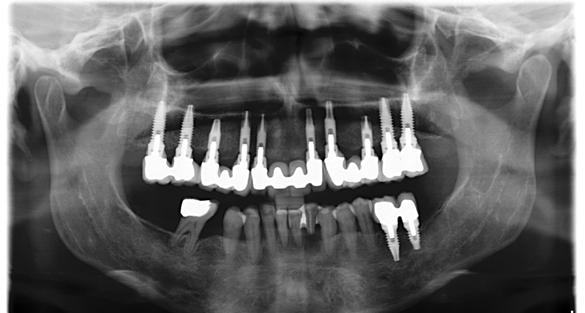

Figura 3. Radiografía tras la colocación de los implantes superiores e inferiores y la carga inmediata del sector anterosuperior.

En el arco superior se planifica una rehabilitación cementada por tramos, que en ese contexto representaba la mejor alternativa en términos de estética y estanqueidad, mediante pilares específicos para fresado. Para ello se programan 10 implantes. En una primera fase se realiza la carga inmediata

del sector anterior y la carga definitiva de los implantes mandibulares mediante una prótesis de resina atornillada (Figura 3).

Seis meses después se cargan los implantes de los sectores posteriores con una prótesis atornillada sobre transepiteliales de larga duración en metal-resina, lo que permite generar una carga controlada y favorecer la adecuada conformación de los tejidos periimplantarios (Figura 4).

Figura 12. Radiografía final con la prótesis cementada en posición.

El mantenimiento periodontal y la implicación de la paciente en las medidas de autocuidado se mantuvieron de forma constante durante 23 años (Figura 25). La ortopantomografía realizada en una de las visitas de control mostró estabilidad completa de los implantes, sin signos radiográficos de pérdida ósea patológica.

Figura 21. Radiografía con la rehabilitación finalizada.

Figura 24. Radiografía a los 5 años que evidencia estabilidad ósea periimplantaria y periodontal.

25. Radiografía a los 25 años con mantenimiento del nivel óseo en implantes y dientes remanentes.